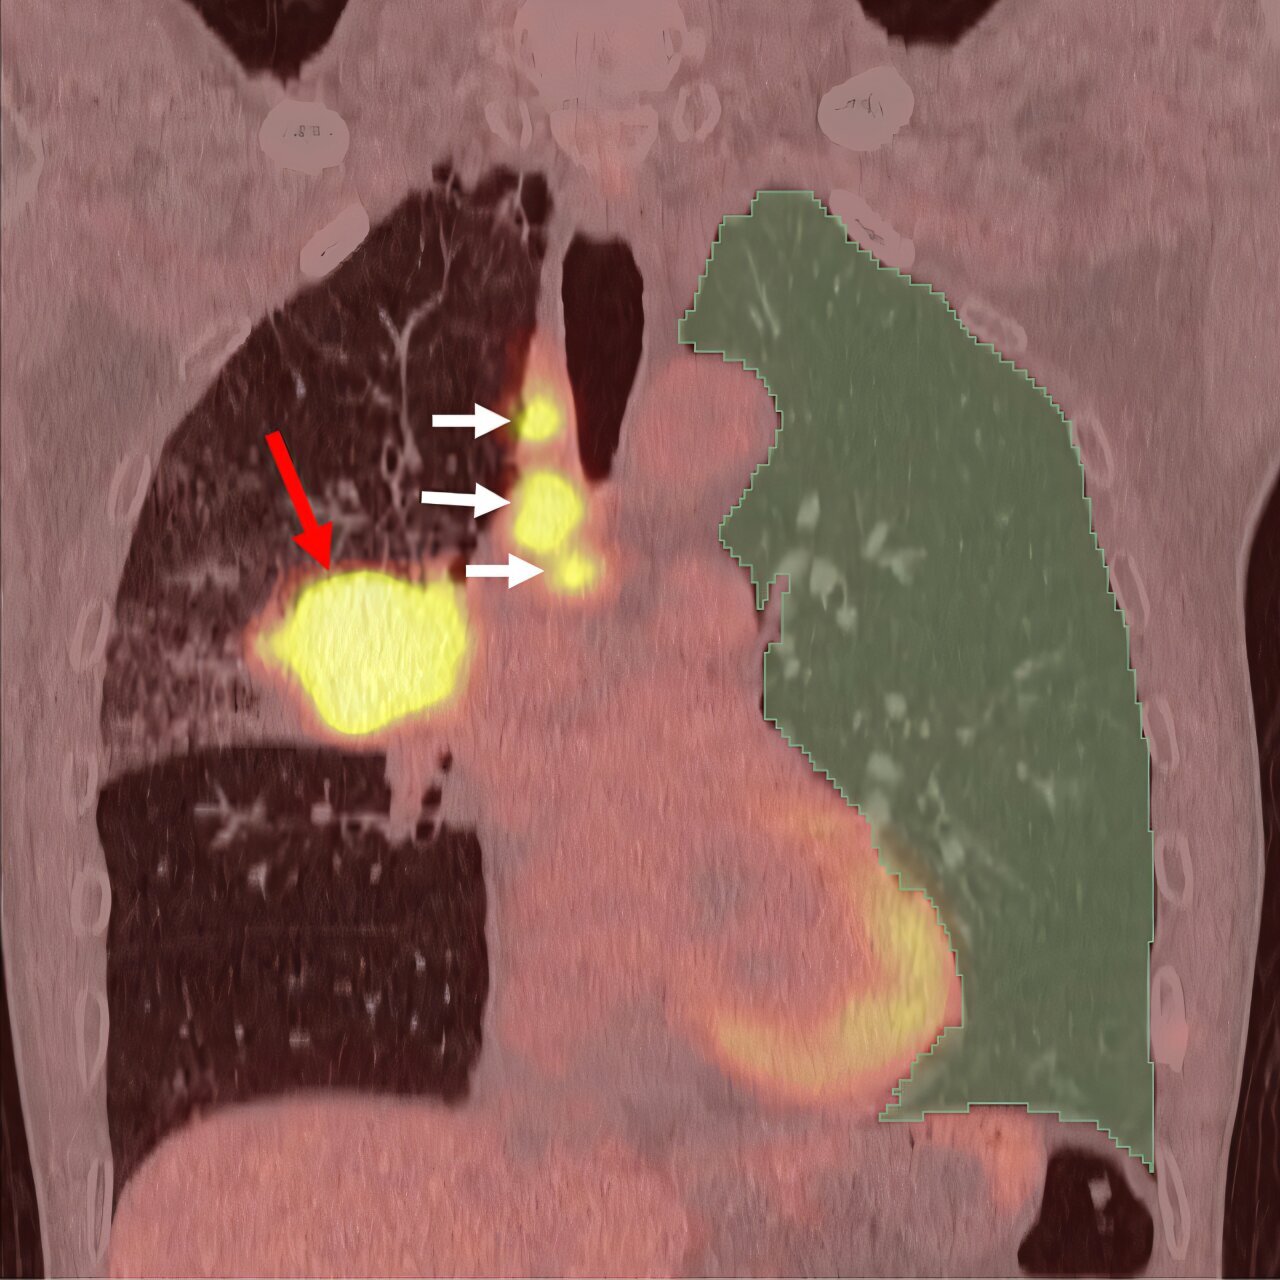

Используя PET/CT-сканирование, ученые смогли оценить степень воспаления в здоровых участках легких и применили ИИ для анализа этих данных. Результаты показали, что риск развития болезни в 6,5 раз выше у пациентов с высоким уровнем воспаления в тканях легких по сравнению с теми, у кого воспаление было минимальным.